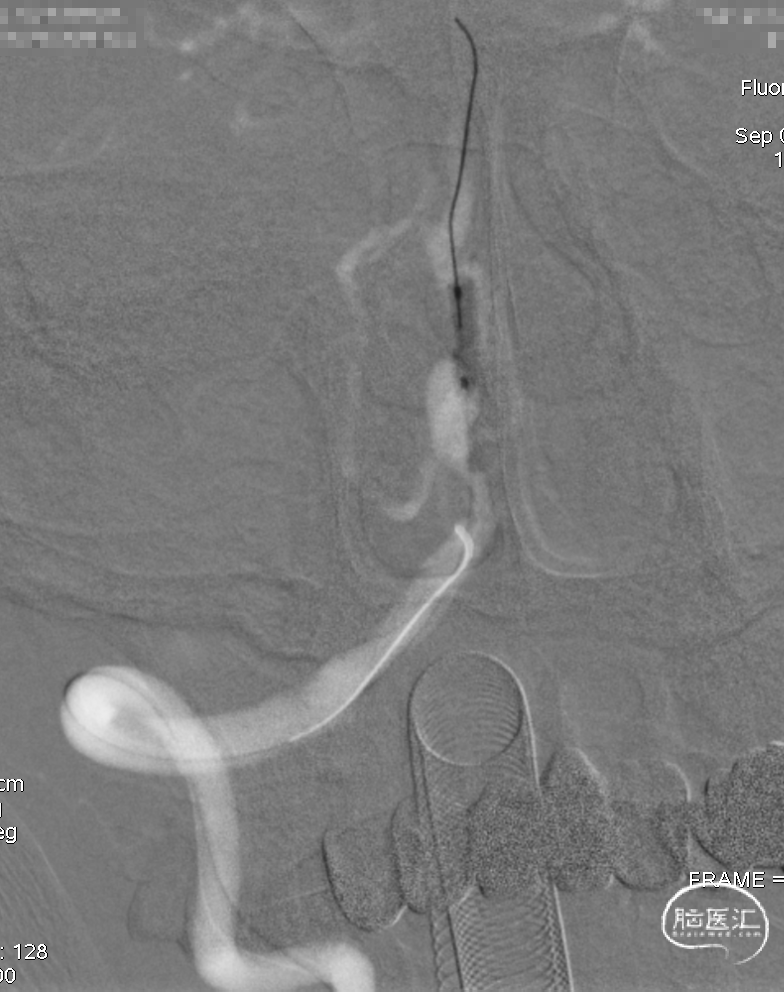

DSA示双侧椎动脉V4段狭窄,右侧为著且合并梭形动脉瘤。

术前DSA。

通桥白驹®球囊(2.5*10),先远后近扩张。

球扩后,狭窄改善。